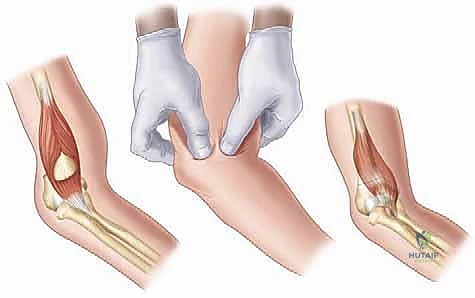

* الرد المغلق (Closed Reduction): يعني إعادة العظام المكسورة إلى مكانها الطبيعي دون الحاجة لعمل شق جراحي كبير لفتح الجلد. يتم ذلك من خلال حركات يدوية دقيقة يقوم بها الجراح.

* التثبيت بالأسلاك عبر الجلد (Percutaneous Pinning): بعد إعادة العظم لمكانه، يتم إدخال أسلاك معدنية دقيقة (K-wires) عبر الجلد لتثبيت العظم ومنعه من الحركة حتى يلتئم.